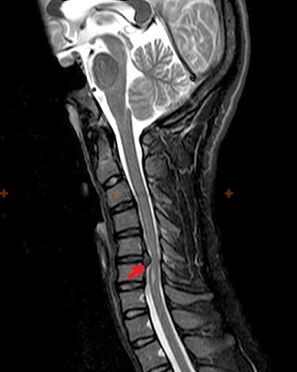

Diagnosztika és röntgen jelek

Az osteochondrosis röntgendiagnózis, mivel a részletes klinikai kép csak az exacerbáció pillanatában áll rendelkezésre, míg a gerinc változásai az ember teljes szubjektív jólétével fordulhatnak elő. Röntgenvizsgálat nélkül csak osteochondrosis gyanújáról beszélhetünk, mert hasonló tüneteket más betegségek is okozhatnak (myositis, csigolya-daganat stb.).

Az osteochondrosis diagnosztizálására a következő kutatási módszereket alkalmazzák: radiográfia (lehetőleg funkcionális tesztekkel), MSCT és MRI. Ez utóbbi vizsgálat a legelőnyösebb, mivel lehetővé teszi az intervertebralis struktúrák állapotának nagyon világos megjelenítését.

Az osteochondrosis röntgenjelei közé tartoznak a következő változások a gerincben:

- Csökkentett csigolyaközi lemezek magassága.

- marginális csontkinövések jelenléte.

- A csigolyák egymáshoz viszonyított elhelyezkedésének megsértése.

- A csigolyatestek és ívek deformációi stb.

A fent leírt változások jelenléte, valamint a csigolyaközi lemez szerkezetének MSCT-vel és MRI-vel kimutatott változásai megbízható jelként szolgálnak, amely megerősíti az osteochondrosis jelenlétét.